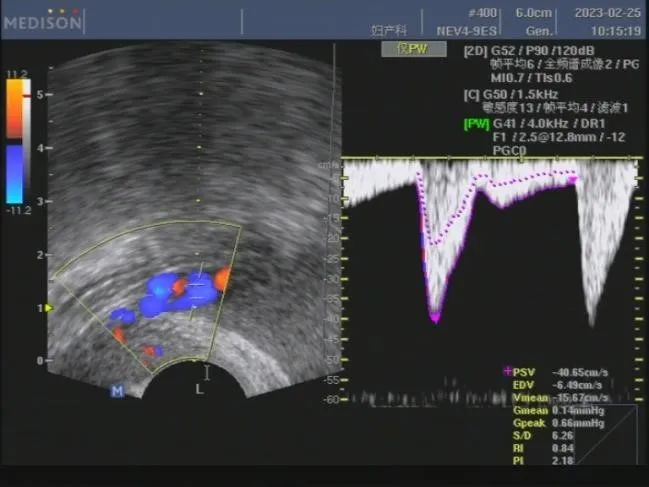

由于彩超具有血流显像功能,能够很好地观测到血管的解剖结构,以及血流速度和状态的改变,这些信息能够提高医生对疾病的诊断能力,从而提高诊断的准确度。

彩超:子宫动脉检查

彩超:胎儿脐动脉检查